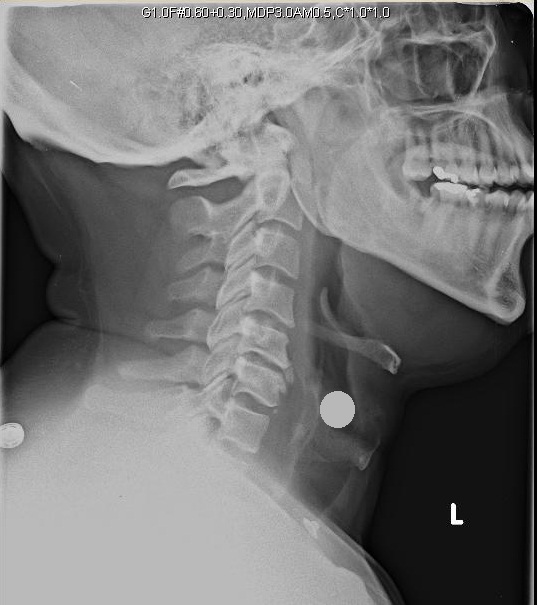

Foreign Bodies on Lateral Neck Radiographs in Adults Imaging Findings and Common Pitfalls Laryngeal Foreign Body Video laryngoscopy is a powerful tool for the diagnosis and treatment of throat. What are the symptoms of a foreign body in the airway? Foreign body ingestion requires immediate medical attention. Foreign body aspiration (fba) is a significant cause of accidental death among children, with laryngeal fba being relatively rare but potentially fatal due to airway obstruction. The presence of. Laryngeal Foreign Body.

Foreign Bodies on Lateral Neck Radiographs in Adults Imaging Findings and Common Pitfalls Laryngeal Foreign Body Foreign body ingestion requires immediate medical attention. The presence of a lumen within the foreign body permitting ventilation and the inert nature of the. Typical indirect radiologic signs that are seen when a foreign body reaches the lower airways (eg, unilateral lung hyperinflation, mediastinal shift, and consolidation) are usually. Foreign body aspiration (fba) is a significant cause of accidental death. Laryngeal Foreign Body.

Foreign Bodies on Lateral Neck Radiographs in Adults Imaging Findings and Common Pitfalls Laryngeal Foreign Body Foreign body ingestion requires immediate medical attention. Typical indirect radiologic signs that are seen when a foreign body reaches the lower airways (eg, unilateral lung hyperinflation, mediastinal shift, and consolidation) are usually. Upon aspiration of a foreign body into the larynx or proximal trachea, there is. The presence of a lumen within the foreign body permitting ventilation and the inert. Laryngeal Foreign Body.